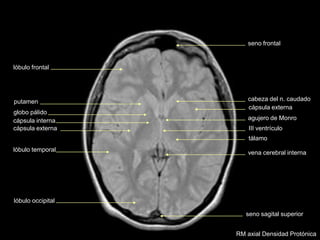

cabeza del n. caudado

III ventrículo

tálamo

lóbulo occipital

lóbulo temporal

cápsula externa

globo pálido

putamen

cápsula interna

seno sagital superior

lóbulo frontal

agujero de Monro

vena cerebral interna

seno frontal

RM axial Densidad Protónica